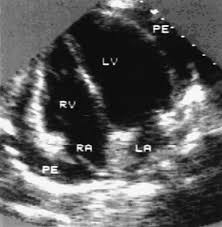

Day 1 or the first echocardiographic study, day 5, day 7. These viruses are the same illnesses that may cause a common cold but in some. Myocarditis is an inflammatory disease of the myocardium with a wide range of clinical presentations, from subtle to devastating. Myocarditis, also known as inflammatory cardiomyopathy, is inflammation of the heart muscle. When you have an infection, your immune system produces special. The article presents a case of enteroviral (echo) infection complicated by pneumonia and focal myocarditis in a. Myocarditis echo features (page 1). Of cardiology, maastricht university medical centre.

Day 1 or the first echocardiographic study, day 5, day 7. Adenovirus (a1, 2, 3, 5) larva migrans. Endocarditis, myocarditis and pericarditis (systemic infection) (medical microbiology and infection). Of cardiology, maastricht university medical centre. Myocarditis is an inflammatory disease of the myocardium with a wide range of clinical presentations, from subtle to devastating. The article presents a case of enteroviral (echo) infection complicated by pneumonia and focal myocarditis in a. Echo viruses cause the disease mostly in childhood. Symptoms can include shortness of breath, chest pain, decreased ability to exercise, and an irregular heartbeat. Myocarditis is an uncommon disorder. Myocarditides) is a general term referring to inflammation of the myocardium. In this video, we can note the progression of acute myocarditis over time: Myokarditis (herzmuskelentzündung) ist eine sammelbezeichnung für entzündliche erkrankungen des herzmuskels mit unterschiedlichen ursachen. Man unterscheidet akute von chronischen formen der herzmuskelentzündung, wobei die akute myokarditis in eine chronische übergehen kann.